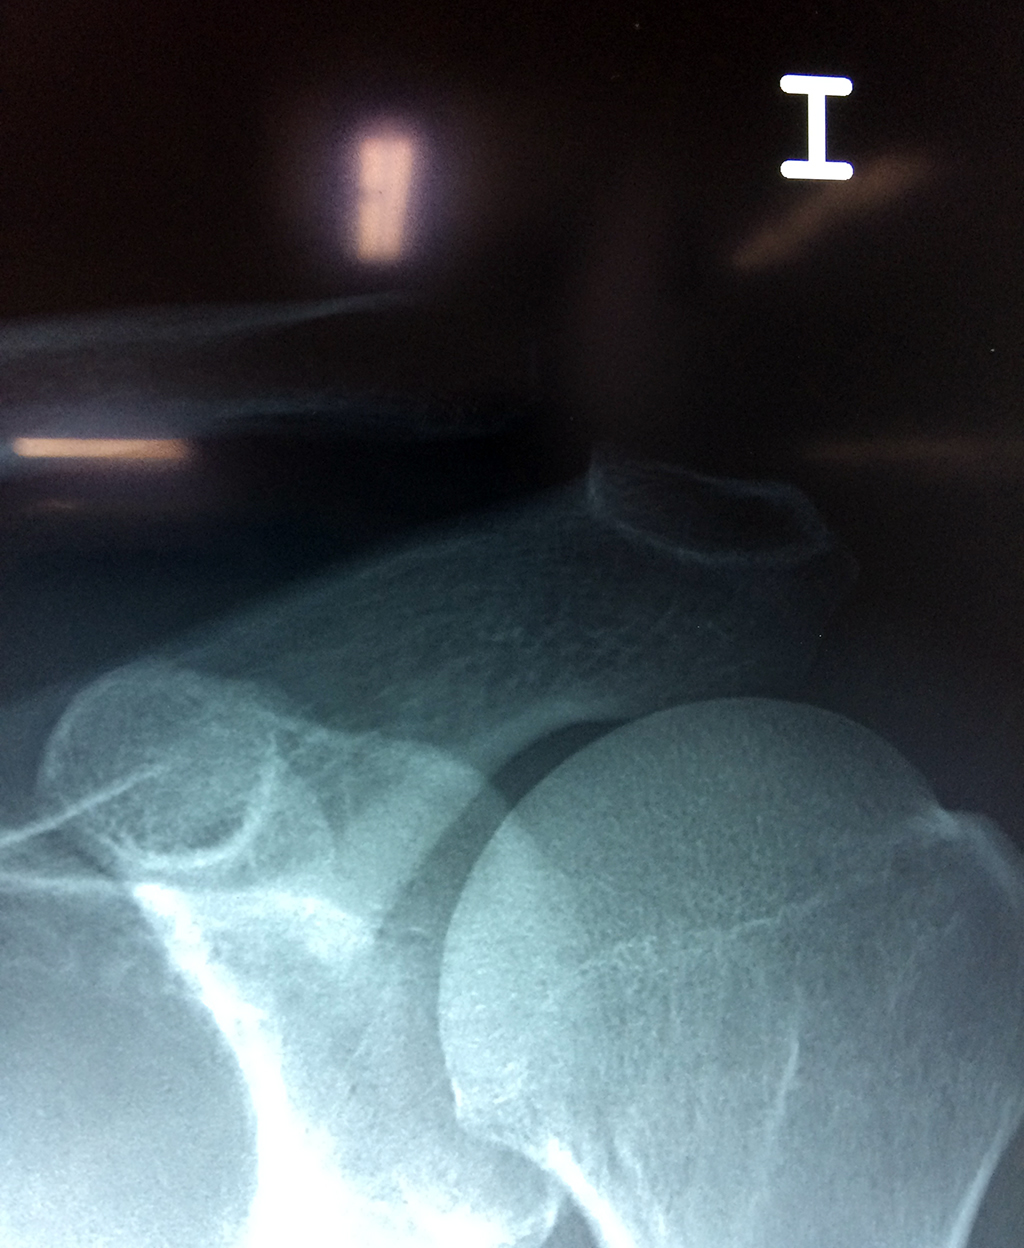

Cirugías de Codos - Clavícula

La clavícula es un hueso largo, con forma de "S" itálica, situado en la parte anterosuperior del tórax. Junto con la escápula forman la cintura escapular. Se puede palpar por toda su longitud y se extiende del esternón al acromion de la escápula, siguiendo una dirección oblicua lateral y posterior.